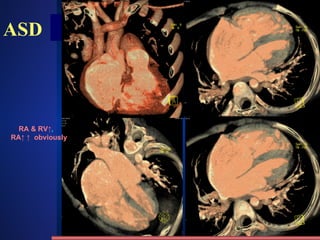

ASD Clinic mostly adult  SM on the 2th-3rd intercostal of the left sternal border Change of hemodynamics X-ray appearance Cardiomegaly , “mitral configuration” RA & RV↑ ,  RA↑ ↑   obviously Pulmonary artery segment bulge  , hilum angiectasia, hilum dance pulmonary blood flow↑ ↑. PAH in later stage LA do not enlarge, LV and aorta shrink /231 4 type: Ostium primum , ostium secundum Sinus venosus , coronary sinus Fossa Ovalis defect 80~90% Atrial septal defect methods normal abnormities diseases

ASD----hemodynamics /231 Left -> right shunt But  depend on the P. Vscular resistance  RA LA RA flow  ↑ RV flow  ↑ PBF↑ RA hypertrophy dilatation RV hypertrophy dilatation pulmonary  hypertension Right heart failure methods normal abnormities diseases

ASD RA & RV↑ ,  RA↑ ↑   obviously

ASD /231 Enlargement of RA methods normal abnormities diseases RA RV PA Aorta svc